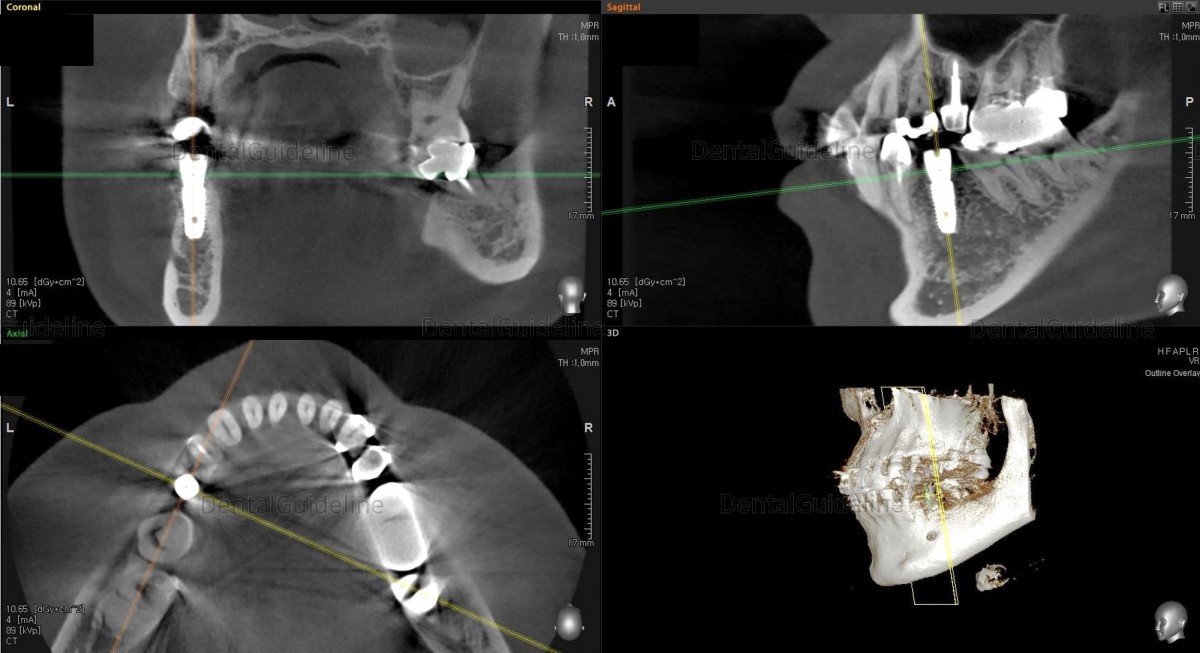

CBCT after implant surgery.